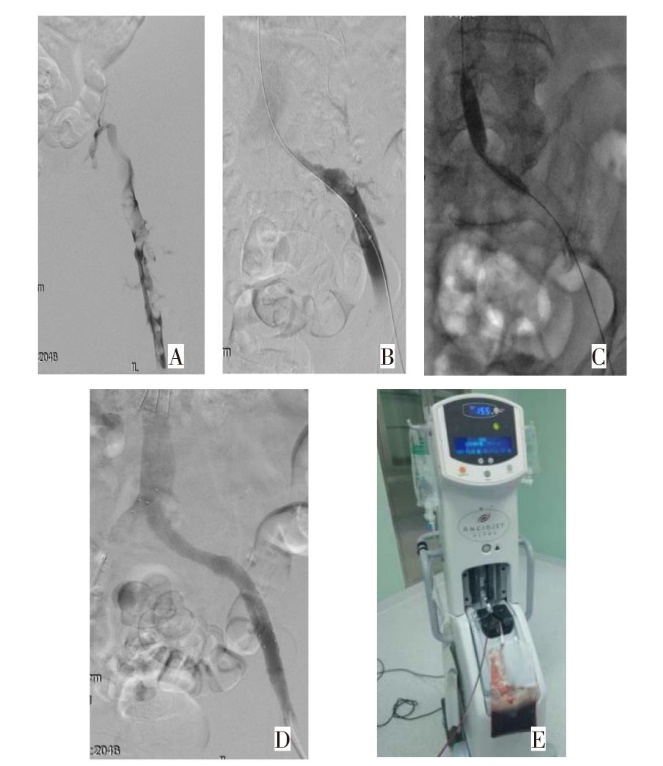

WANG Guohua, CHEN Baoxing, LI Huipeng, GUO Pengwei, ZHANG Hua. Comparison of therapeutic effects between AcoStream and AngioJet in acute iliofemoral vein thrombosis[J]. Tianjin Medical Journal, 2025, 53(1): 52-56.